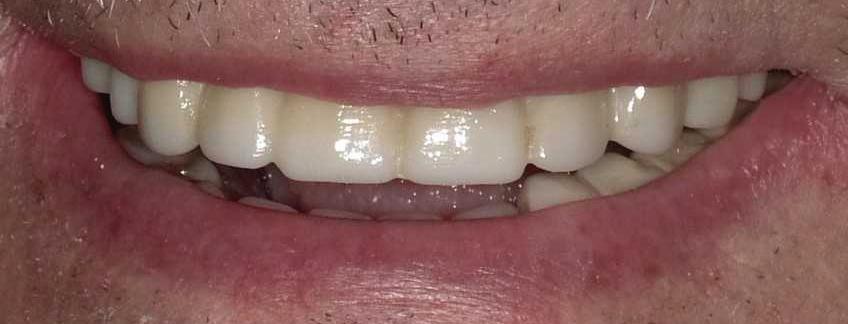

A Reason To Smile Again

Dental Implants

Can just four implants replace all of the teeth on the top or the bottom of your mouth? Thanks to advances in dental implant technology, that answer is a resounding yes.

Believe it or not, tooth loss is extremely common among adults, especially as we age. In fact, more than 35 million people in America are missing

all of their upper and/or lower teeth. Rather than living with the discomfort and hassles of dentures, many people are opting for what is called “all-onfour” dental implant restoration.

All-On-Four: One Full Arch Of Teeth, Four Dental Implants

To fully understand this remarkable technique for replacing teeth, you should first understand what a dental implant is. An implant is a small titanium screw that fits inside your jawbone and replaces the root-part of a missing tooth. Minor surgery is required to insert the implants. Once the implant is in place, a crown is attached to give you a highly realistic-looking and functional prosthetic tooth. Here’s where it gets really interesting: You do not need a dental implant for each and every one of your missing teeth. All you need is four precisely placed implants on the top of your